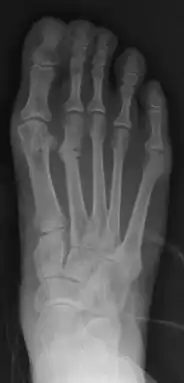

March fracture, is the fracture of the distal third of one of the metatarsals occurring because of recurrent stress. It is more common in soldiers, but also occurs in hikers, organists, and people whose duties entail much standing (such as hospital doctors). March fractures most commonly occur in the second and third metatarsal bones of the foot.[1][2][3] It is a common cause of foot pain, especially when people suddenly increase their activities.[4]

X-ray is seldom helpful, but a CT scan and an MRI study may help in diagnosis.[5] Bone scans are positive early on. Dual energy X-ray absorptiometry is also helpful to rule out comorbid osteoporosis.[6]